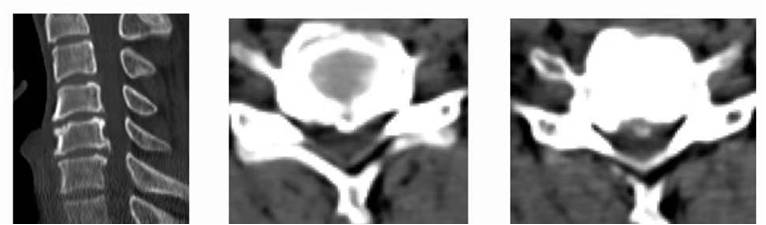

查新报告1

查新报告2